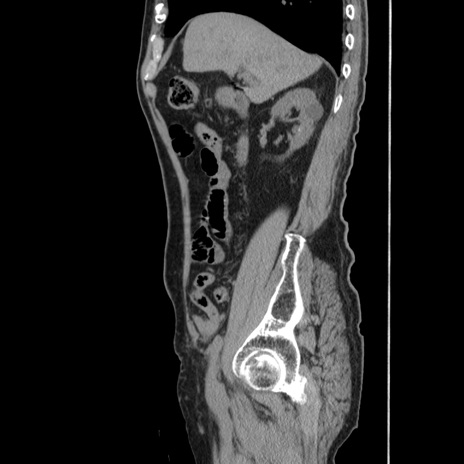

症例24(矢状断像)

【症例】80歳代男性

【主訴】左側腹部痛、嘔吐

【現病歴】本日早朝より左腹部に痛みあり。昼頃嘔吐認めたため、救急要請。

【既往歴】直腸癌(Mile手術)、胆摘

【身体所見】意識清明、BT 35.9℃、BP 221/93mmHg、SpO2 97%(RA) 、腹部:左ストーマ周囲に限局性の腹部膨隆あり。 膨隆部自発痛・圧痛あり・軟。

【データ】WBC 7700、CRP 0.09